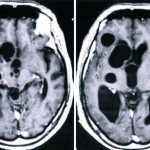

Электрофизиологические, томографические и прочие инструментальные диагностические методы также пока не приносят исчерпывающей информации о связях между заиканием и органическими изменениями в структурах головного мозга, – в частности, зоны Брока́, функционирование которой непосредственно ассоциировано с речью.

- невролог проводит исследование с целью выявления отклонений в нервной системе. Для этого используются рентгенография черепа, электроэнцефалография, реоэнцефалография, МРТ, КТ;